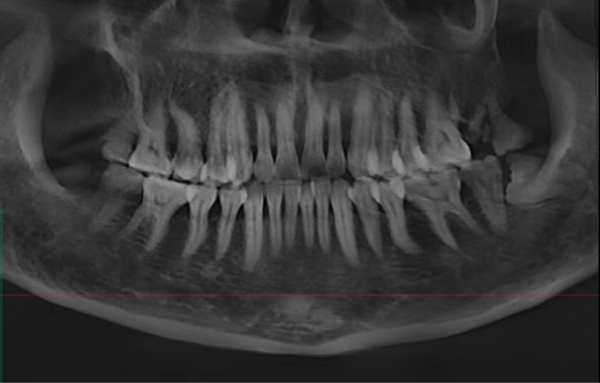

“最开始她以为是之前治疗过的那颗牙(右上第一前磨牙)又出问题了,但我们仔细检查后发现,真正让她痛得睡不着的是另一颗快被蛀空的大牙(右上颌第二磨牙)。”黄医生回忆道,“那颗牙表面已经蛀得不成样子,一碰冷水就疼得直抽气,轻轻敲击也疼得厉害。当时她特别担心要反复治疗,我们就商量着把两颗邻近的牙一起做了根管治疗,也避免她来回奔波。”

黄小艳:根管治疗并非万能,一般我们会通过CBCT来评估牙齿的保留价值,最终方案需结合患者的具体情况。以下情况建议优先考虑种植牙: